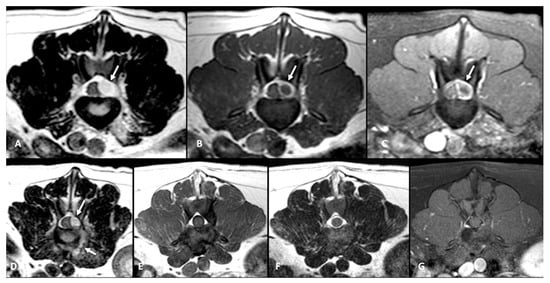

All dogs had an MRI of the spine within 24 h of presentation (Figure 1A–C, Figure 2A and Figure 3A–D). The images revealed the presence of a space-occupying accumulation of epidural material suggestive of empyema. The epidural material was hyperintense or had a mixed (hyperintense and isointense) signal on T2W sequences compared to the spinal cord and had an iso to hypointense signal on T1W sequences. After contrast administration, enhancement was observed in all cases with variable patterns (diffuse, heterogeneous, or ring-like).

Follow-up MRI studies were performed (n = 13) from 2 to 5 months after treatment initiation, in 8/13 dogs conservatively treated (Figure 1D–F) and in 5/13 of the dogs surgically treated (Figure 2B and Figure 3E–G). Radiological improvement was noticed in all dogs, considering there were no signs of epidural material or soft tissue enhancement. Bone changes (osteoproliferation and mild contrast enhancement) were still present.

Figure 1. MRI transverse planes at the level of T13-L1 intervertebral disc at time of presentation (AC) and follow-up at 4 months (DF) in a dog diagnosed with SEE conservatively treated. A left dorso-lateral epidural lesion hyperintense on T2-W (arrow, A) and hypointense on T1-W (arrow, B) is displacing the spinal cord. On the T1-postcontrast image there is a ring enhancement of the epidural lesion (arrow C) and irregular soft tissue enhancement around the intervertebral disc, which shows irregular shape, and heterogeneous hyperintense signal on the T2-W image (A). On the follow-up images on T2-W (D), T1-W (E) and T1-W postcontrast (F) there are no signs of the previous epidural lesion nor the contrast enhancement.